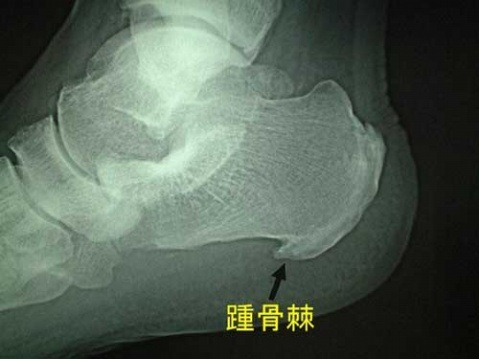

clip_image003

跟骨骨刺的有无,通常使用X光照片可以明确。

对于跟骨刺的形成,过去认为是由于长期行走和长时间站立而引起的退行性病变,但这一理论对很多因骨质增生而产生的临床表现无法做出确切的解释。最近的理论是“足部力学的动态平衡失调",造成跖长韧带,跖筋膜挛缩,引起跟骨附着点处持续性的牵拉损伤,韧带与筋膜的纤维就会不断地被撕裂,与此同时人体自身就会通过代偿机制的保护作用,把大量钙与磷输送到被撕裂的韧带与筋膜的附着点处,以加强韧带和筋膜的附着点处不被拉伤或拉脱,久而久之这些大量聚集的钙质与磷会使韧带与筋膜附着点钙化骨化,从而产生足跟骨骨刺这一病理现象。

足跟出现疼痛与跟骨骨刺有一定关系,但并非完全由跟骨骨刺引起。赵幼林医师观察了229例病人,经照片证明有跟骨刺的顽固性跟痛症患者中,110例单足痛,但两侧均有骨刺;14例双足痛,仅单侧有骨刺;10例骨刺发生于无痛侧。

早在1915年,就有人认为跟跖侧痛与跟骨骨刺有关,但它们间的确切关系目前仍不十分清楚。在跟跖侧痛患者中,约50%的患者有跟骨骨刺存在,但许多有跟骨骨刺的人并无跟跖痛。Shmokler观察发现在有跟骨骨刺的人群中,仅5.2%发生过跟跖侧痛。Tanz观察100例无跟痛的患者,发现有16%的患者有跟骨骨刺跟骨骨刺仅是一个X线片表现,可能源于跖筋膜等劳损引起的慢性炎症。跟跖侧疼痛的程度与骨刺大小不成正比,绝大多数骨刺并无疼痛。

另外说明一下,在最新的《足踝外科学》中,没有单独把跟骨骨刺作为病种来看待,只是一个病理现象。